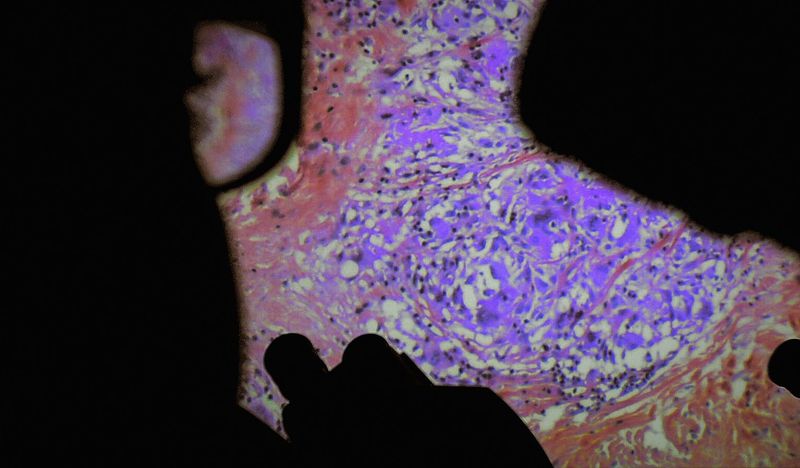

《人體萬花胴》電影海報

解剖學發明以降,人體奧秘開始為世人所知所見。然而,大家習慣的始終是那副最表面的臭皮囊,或留戀或厭倦,或擁抱或憎惡。假如能深入體腔,即時觀察微肌細理,體液流動,可會了悟箇中奧妙,那欲肉不為肉所欲的真義?得到醫院前線及技術人員協助,韋蓮娜柏麗芙與路西安卡斯當泰來再現了內窺和微創手術的影像,輔以病人和醫護的生活點滴,讓作為關懷、痛苦、希望和被宰制場所的身體,成了光影景觀的主角。血肉不再模糊的結果,可會對人文多一份凝視?